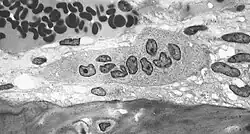

Osteoclasto (do grego para "osso" (Οστό) e "quebrado" (κλαστός)) é uma célula móvel, gigante e extensamente ramificada, com partes dilatadas, e é multinucleada. Os osteoclastos foram descobertos por Kolliker em 1873.[1]

Nas áreas de reabsorção de tecido ósseo encontra-se porções dilatadas dos osteoclastos, colocadas em depressões da matriz escavadas pela atividade dos osteoclastos e conhecidas como lacunas de Howship. Os osteoclastos tem citoplasma granuloso, algumas vezes com vacúolos, fracamente basófilo nos osteoclastos jovens e acidófilos nos maduros.

Estas células se originam de precursores mononucleados provenientes da medula óssea que, ao contato com o tecido ósseo, unem-se para formar os osteoclastos multinucleados. A superfície ativa dos osteoclastos, voltada para a matriz óssea, apresenta prolongamentos vilosos irregulares.

A maiorias desses prolongamentos tem a forma de folhas ou pregas que se subdividem. Circundando essa área com prolongamentos vilosos, existe uma zona citoplasmática, a zona clara, pobre em organelas porém com muitos filamentos de actina. A zona clara é um local de adesão do osteoclasto com a matriz óssea e cria um microambiente fechado, ácido (H+), colagenase e outras hidrolases que atuam localmente digerindo a matriz orgânica e dissolvendo os cristais de sais de cálcio.

Os osteoclastos são células muito grandes, que tem cerca de 40 micrómetros de diâmetro. Possuem vários núcleos e são responsáveis pela destruição do osso. Quando a membrana celular dos osteoclastos entra em contato com a matriz óssea formam-se prejecções que constituem um bordo pelo qual entram íons hidrogênio para assim ser produzido um meio ácido que provocará a descalcificação da matriz óssea. Nos osteoclastos o retículo endoplasmático rugoso é escasso, e o complexo de Golgi é extenso.[2][3]